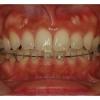

증산댁의 덧니 치아교정후기 ③② 스케일링 & 당기기

증산댁의 덧니 치아교정후기 ③② 스케일링 & 당기기 안녕하세요 ~~~ 넘넘 오랜만의 치아...

증산댁의 덧니 치아교정후기 ③① 다시 당기기 ~~~

증산댁의 덧니 치아교정후기 ③① 다시 당기기 ~~~ 안녕하세요 ~~~ 오랜만에 쓰는 치아교...